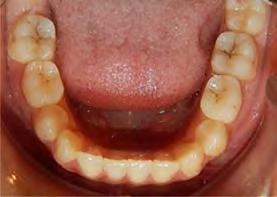

El tiempo de tratamiento fue de 2 años y 9 meses se lograron los objetivos del tratamiento manteniendo el perfil facial, y las relaciones esqueléticas maxilomandibulares. Se realizó la tracción del 13, la corrección de rotaciones dentales en el maxilar, se mantuvo la clase I molar izquierda y se obtuvo la clase I molar derecha. La clase I canina izquierda, y se logró la clase I canina derecha, cerrar mordida abierta de sectores laterales, corrección del overjet y overbite, corrección de líneas medias dentales, manejo de Bolton de arcada superior, mejorar estado periodontal, lograr correcta intercuspidación, guía de desoclusión canina y guía incisiva y la restauración de los dientes 12 y 22

(Figura 5). Una vez terminado el tratamiento, la estabilidad a largo plazo mediante la retención con un circunferencial con finger en los incisivos 12 y 22 para la arcada superior y retenedor termoformado para la arcada inferior.

Radiografía panorámica final el canino 13 es incorporado al arco (Figura 5) y los terceros molares en etapa de formación.

Estudios intraorales finales en las fotografías oclusales, se ven los laterales 12 y 22, así como la incorporación del canino al arco con torque adecuado (Figura 6). En la lateral derecha e izquierda la restauración estética de los laterales superiores,

Figura 4. Vista oclusal superior e inferior.

sin rotaciones ni discrepancia de Bolton.

Figura 5. Radiografía Panorámica. Figura 6. Comparación inicio-final en oclusión.